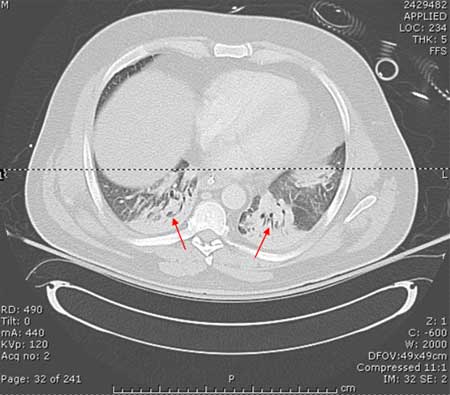

CT scan showing bibasilar opacities of patient with HAP

Consent obtained at University of Louisville, KY